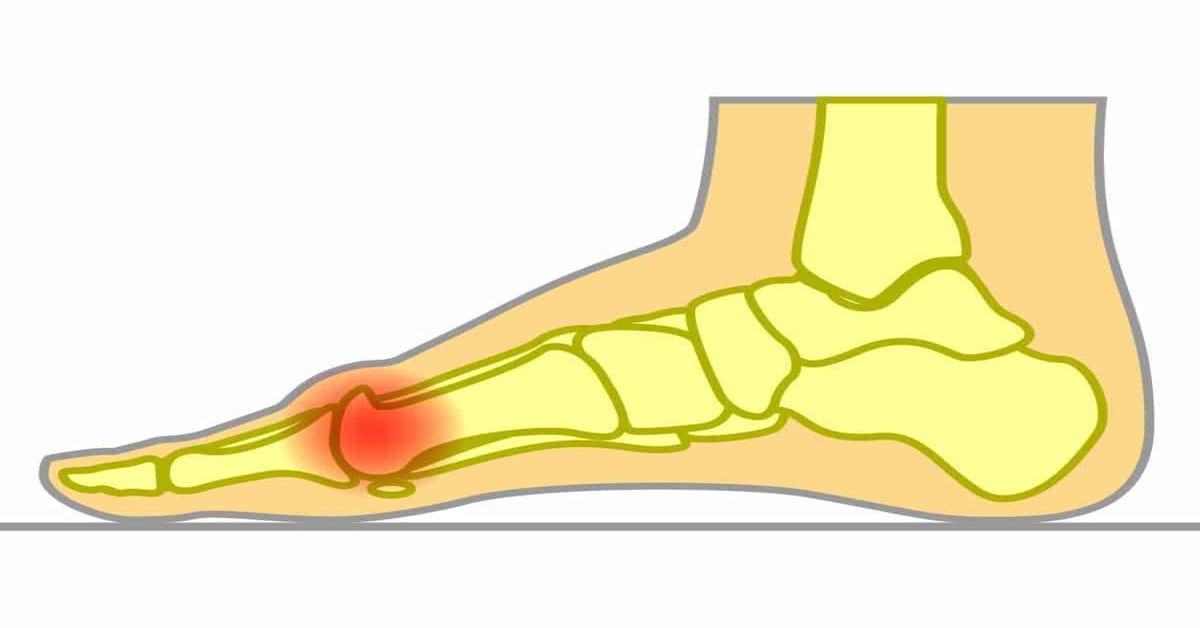

Ayak başparmağının tabanındaki eklemde meydana gelen kireçlenme ve hareket kısıtlılığıyla karakterize bir ayak rahatsızlığıdır. Halluks rijidus nedir? Başparmak ekleminde sertleşme oluşur. Zamanla parmağın yukarı doğru hareketi zorlaşır. İlerleyen dönemlerde eklemde ağrı, şişlik ve günlük hareketleri etkileyen sertlik görülebilir.

Ayak başparmağı ekleminde gelişen kireçlenme ve hareket kısıtlılığıyla ortaya çıkar. Bu hastalığın en yaygın belirtisi, başparmak ekleminde hissedilen ağrı ve sertliktir. Özellikle yürürken, koşarken ya da merdiven çıkarken ağrı artabilir ve günlük hareketleri zorlaştırabilir. Bu durumda ayak cerrahi tarafından detaylı bir değerlendirme yapılması gerekir.

Başparmağın yukarı doğru hareketi zamanla kısıtlanır ve parmak hareket ettirildiğinde zorlanma hissi oluşabilir. Hastalık ilerledikçe eklem çevresinde şişlik ve hassasiyet gelişebilir. Ayakkabı giyerken başparmak üzerindeki baskı artabilir. Bu durum rahatsızlık hissini daha belirgin hale getirebilir.

Bir diğer önemli belirti ise eklem üzerinde kemiksi çıkıntı oluşmasıdır. Bu çıkıntı zamanla büyüyebilir ve ayakkabı içinde sürtünmeye neden olarak ağrıya yol açabilir. Bazı kişilerde başparmak hareketi kısıtlandığı için yürüyüş şekli değişebilir ve ayağın diğer bölgelerinde de ağrı oluşabilir.

Halluks rijidus, ayak başparmağının tabanındaki eklemde zamanla gelişen kireçlenme ve hareket kısıtlılığı sonucu ortaya çıkar. Bu durum genellikle eklemin uzun süre aşırı yük altında kalması ve zamanla yıpranmasıyla ilişkilidir. Eklem yüzeyindeki kıkırdak dokunun aşınması, hareket sırasında ağrı ve sertlik oluşmasına neden olur.

Halluks rijidus, ayak başparmağının tabanındaki eklemde gelişen kireçlenme sonucu ortaya çıkan bir ayak rahatsızlığıdır. Zamanla parmak hareketinin kısıtlanmasına neden olur. Bu hastalıkta başparmak eklemi zamanla sertleşir ve özellikle parmağın yukarı doğru hareketi zorlaşır. Yürüyüş sırasında ağrı, şişlik ve hareket kısıtlılığı günlük yaşam konforunu olumsuz etkileyebilir.

Rahatsızlık genellikle yürürken, koşarken veya merdiven çıkarken başparmak ekleminde ağrı hissiyle fark edilir. Hastalık ilerledikçe eklem üzerinde kemiksi çıkıntılar oluşabilir ve ayakkabı kullanımı sırasında baskıya bağlı ağrı artabilir. Zamanla yürüyüş şekli değişebilir ve ayağın diğer bölgelerinde de rahatsızlık oluşabilir.